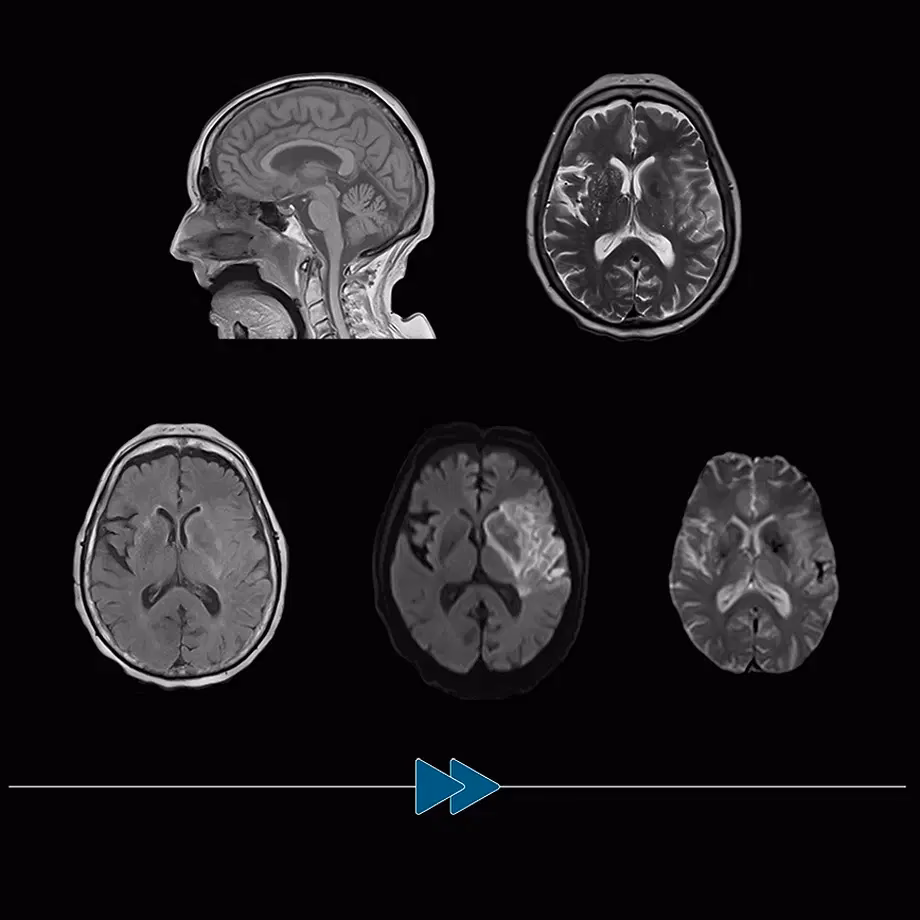

La Resonancia Magnética, a menudo conocida por sus siglas en inglés MRI (Magnetic Resonance Imaging), es una poderosa herramienta de diagnóstico no invasivo. Su principal función es generar imágenes detalladas de los órganos y tejidos internos del cuerpo. Utiliza un potente imán para alinear los protones de los átomos de hidrógeno en el agua y la grasa del cuerpo, y luego aplica ondas de radio para perturbar esta alineación. Cuando los protones vuelven a su estado original, emiten señales que son detectadas por una antena y procesadas por una computadora para crear imágenes en 'cortes' o planos del cuerpo. La RM es excepcional para visualizar la estructura anatómica con gran detalle, permitiendo identificar la forma, el tamaño y la ubicación de diferentes partes del cerebro, así como detectar anomalías estructurales como tumores, quistes o áreas de daño por accidente cerebrovascular.

Mientras que la RM se centra en la anatomía, la Espectroscopia por Resonancia Magnética (ERM), o MRS (Magnetic Resonance Spectroscopy) por sus siglas en inglés, va un paso más allá. No crea imágenes en el sentido tradicional, sino que mide los cambios bioquímicos dentro de los tejidos. Utiliza la misma máquina de RM, pero con secuencias de pulsos de radiofrecuencia adicionales y análisis de señales más complejos. La ERM se enfoca en detectar y cuantificar la presencia de diferentes metabolitos químicos, que son productos del metabolismo celular, dentro de un área específica de interés en el cerebro o la médula espinal.

La distinción más fundamental entre la RM y la ERM radica en el tipo de información que proporcionan. La RM es una herramienta de imagen *anatómica*. Nos muestra dónde están las cosas: la ubicación exacta de un tumor, la extensión de una lesión, el tamaño de una estructura cerebral particular. Es como un mapa detallado del terreno.

Por otro lado, la ERM es una herramienta de análisis *químico* o *metabólico*. Nos dice de qué están hechas las cosas en una región específica. En lugar de ver la estructura física de un tumor, la ERM nos revela su composición química, comparándola con el tejido cerebral sano circundante. Es como un análisis del suelo en un punto específico del mapa, indicando los nutrientes o sustancias presentes.